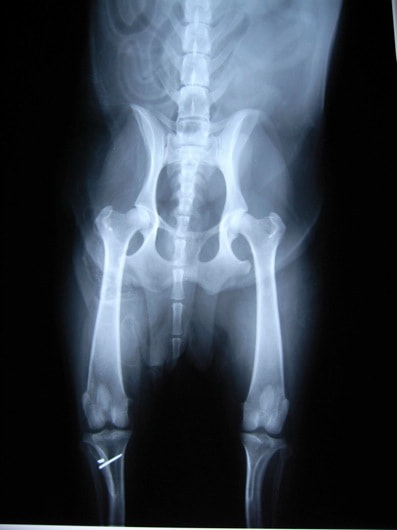

■ 症例22 ポメラニアン 1歳5か月 去勢雄

左後肢の挙上を主訴に来院した。整形学的検査、レントゲン検査より左右の膝蓋骨脱臼(左GradeⅡ〜Ⅲ、右Grade Ⅱ)を認めた。また、脛骨の前方引き出し試験の際に、引き出し兆候は認められないものの、疼痛が認められたため、前十字靭帯の損傷が疑われた。術中における、目視および関節内の操作によって、前十字靭帯の損傷や過伸展といった異常が認められなかったため、膝蓋骨脱臼の整復のみ実施した。手術手技は縫工筋及び内側広筋の解放、脛骨粗面の外側転位、滑車ブロック形造溝術、内外側関節包の縫縮を実施した。本症例は跛行もなく経過良好である。しかし、頸骨高平部の角度(TPA)が 右26.2°、左24.9°であり、解剖学的に前十字靭帯損傷のリスクが高いことから今後の経過に注意が必要である。